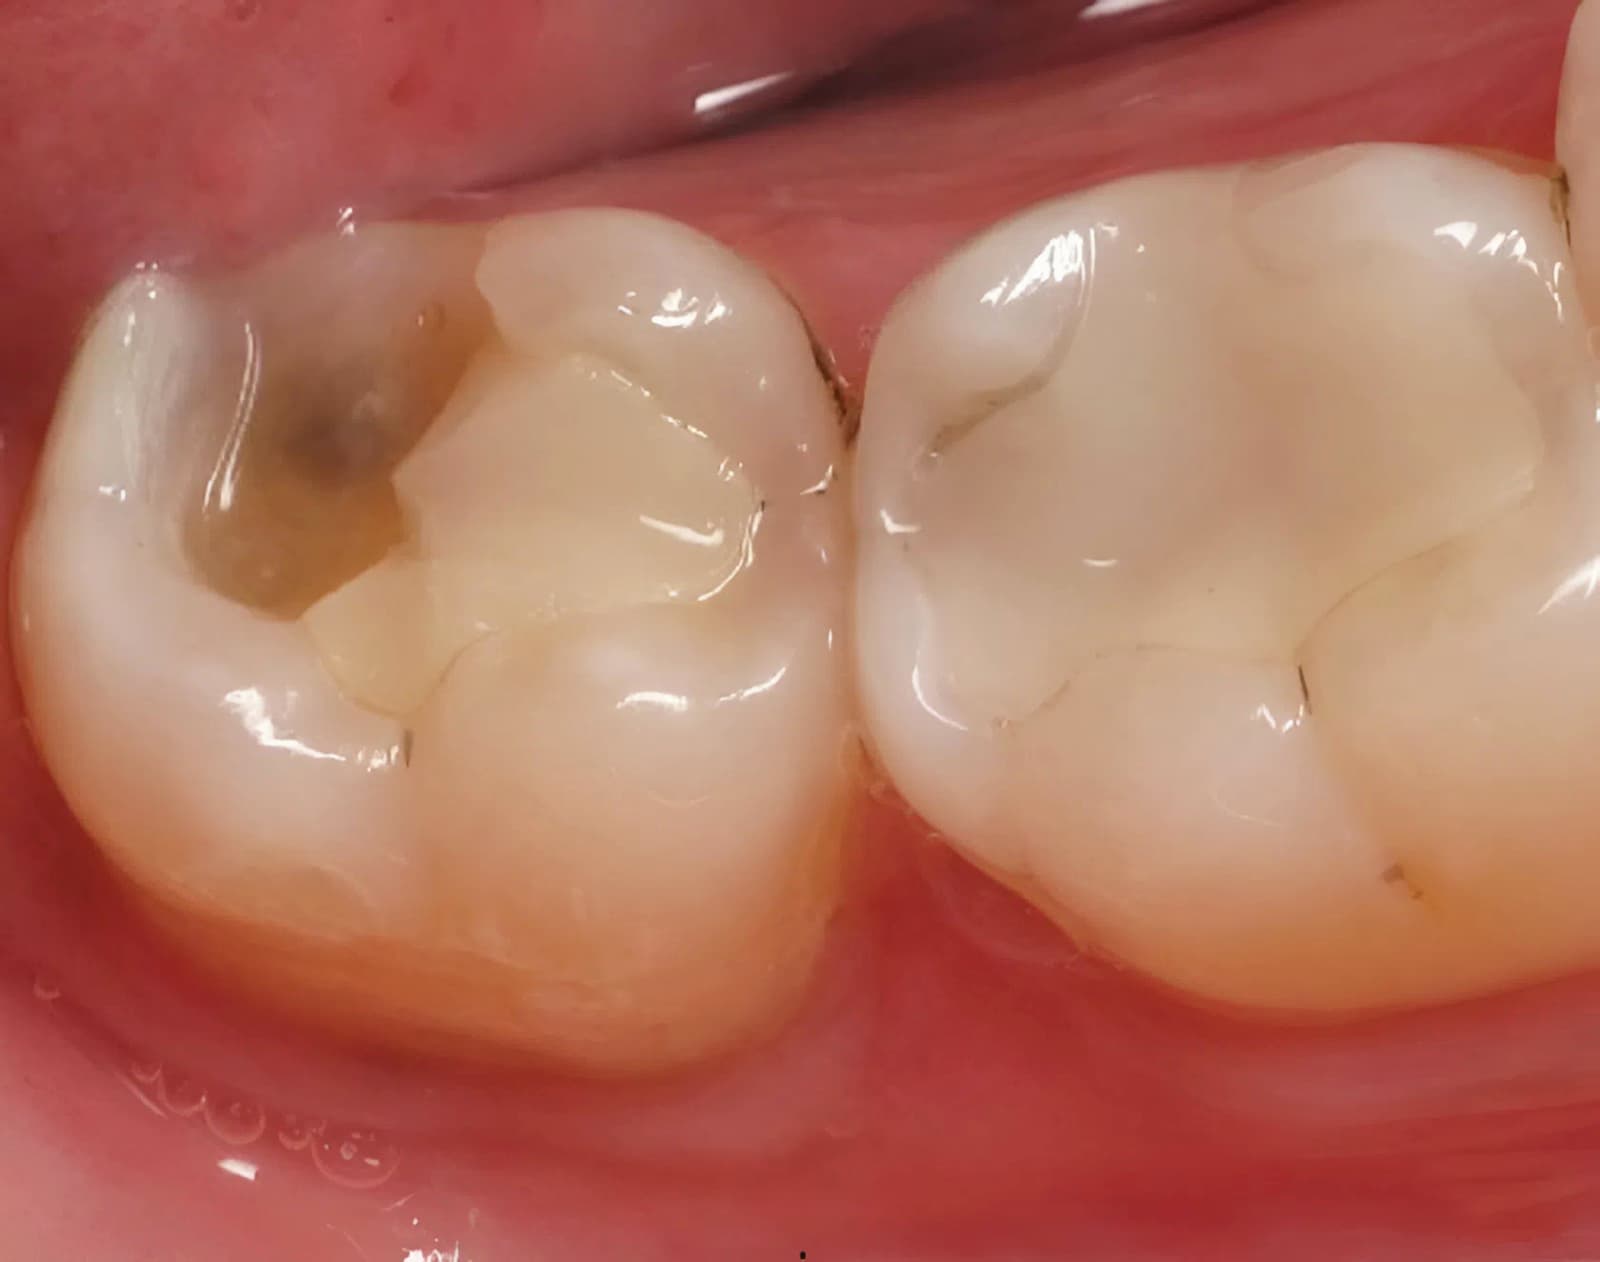

Trường hợp răng còn phục hình được bác sĩ sẽ chỉ định chữa tủy. Để điều trị bác sĩ sẽ tiến hành gây tê, dùng thiết bị khoan chuyên dụng để tạo 1 lỗ nhỏ thông với tủy viêm. Sau khi lấy hết tủy chết ra bên ngoài bác sĩ sẽ tiến hành trám hoặc bọc sứ để khôi phục lại mô răng thật và cải thiện tính thẩm mỹ.

(Kết quả chữa tủy được thực hiện tại Peace Dentistry)(**)